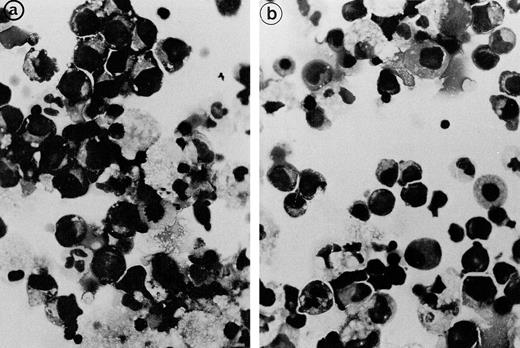

Bone marrow aspirates from the 3 patients showed marked hypercellularity and erythroid hyperplasia (>70% for case nos. 1 and 2). Bone marrow smear from patient 3 showed diffuse lymphocytic infiltration (86%) and numerous erythroid islands (Fig1). The main abnormalities observed in the bone marrow smears of the 3 patients were the presence of numerous erythroid islands, with aggregated erythroblasts and frequent binuclear forms. Most often, adjacent cells shared the appearance of the same maturation stage, but some cells of apparently different maturity were also in close contact. A nonbasophilic clear area was observed at sites of close proximity between adjacent erythroblasts. This feature allowed a distinction to be made between this type of erythroid island and that of sideroblastic anemia. No macrophages were found in contact with these erythroblast clusters.

Bone marrow smear (patient 2): The erythroblasts are numerous and several of them are closely apposed to each other. At the intercellular junction, a clear nonbasophilic zone is evident.

Bone marrow smear (patient 2): The erythroblasts are numerous and several of them are closely apposed to each other. At the intercellular junction, a clear nonbasophilic zone is evident.

The erythroblastic synartesis could be reproduced in vitro: indeed, erythroblast cultures established with bone marrow progenitors from cases 2 and 3 displayed similar morphological abnormalities to those observed in vivo (Fig4a, see page 3686). Crossed culture experiments using the patient erythroblasts grown in the presence of their own serum or of a control serum, or using erythroblasts of a control subject grown in the presence of the patient sera (see Table1) were performed and gave the following results: the erythroblast abnormalities reproduced in culture in the presence of autologous serum were absent when the culture was performed with a control AB serum (Fig 4b). Electron microscopy confirmed these findings, showing that the same intercellular junctions were observed when the patient erythroblastic progenitors were cultured with autologous serum, but that they were absent when the culture was performed in the presence of a control serum. These abnormalities were not reproduced in vitro when the erythroblasts were grown in the patient sera that had been IgG depleted. This allowed us to conclude that the synartesis was caused by an IgG component. Further confirmation was given by the observation that cultured normal erythroblasts displayed authentic synartesis when grown in the presence of patient to serum. Finally, the IgG fractions from the patients were added to normal serum at a concentration of 2 g/L and were able to induce typical synartesis on control erythroblasts grown in this preparation (Fig 5).

Light microscopical aspect of the erythroblasts cultured from patient 2 bone marrow. (a) In the presence of autologous serum: The erythroblasts are closely apposed to each other with occasional nonbasophilic areas present at their junction, mimicking the morphology of the bone marrow smears. (b) In the presence of a control serum: The grown erythroblasts are scattered and individually disposed on this cytospun preparation and do not display the characteristic abnormalities of the disease.

Light microscopical aspect of the erythroblasts cultured from patient 2 bone marrow. (a) In the presence of autologous serum: The erythroblasts are closely apposed to each other with occasional nonbasophilic areas present at their junction, mimicking the morphology of the bone marrow smears. (b) In the presence of a control serum: The grown erythroblasts are scattered and individually disposed on this cytospun preparation and do not display the characteristic abnormalities of the disease.